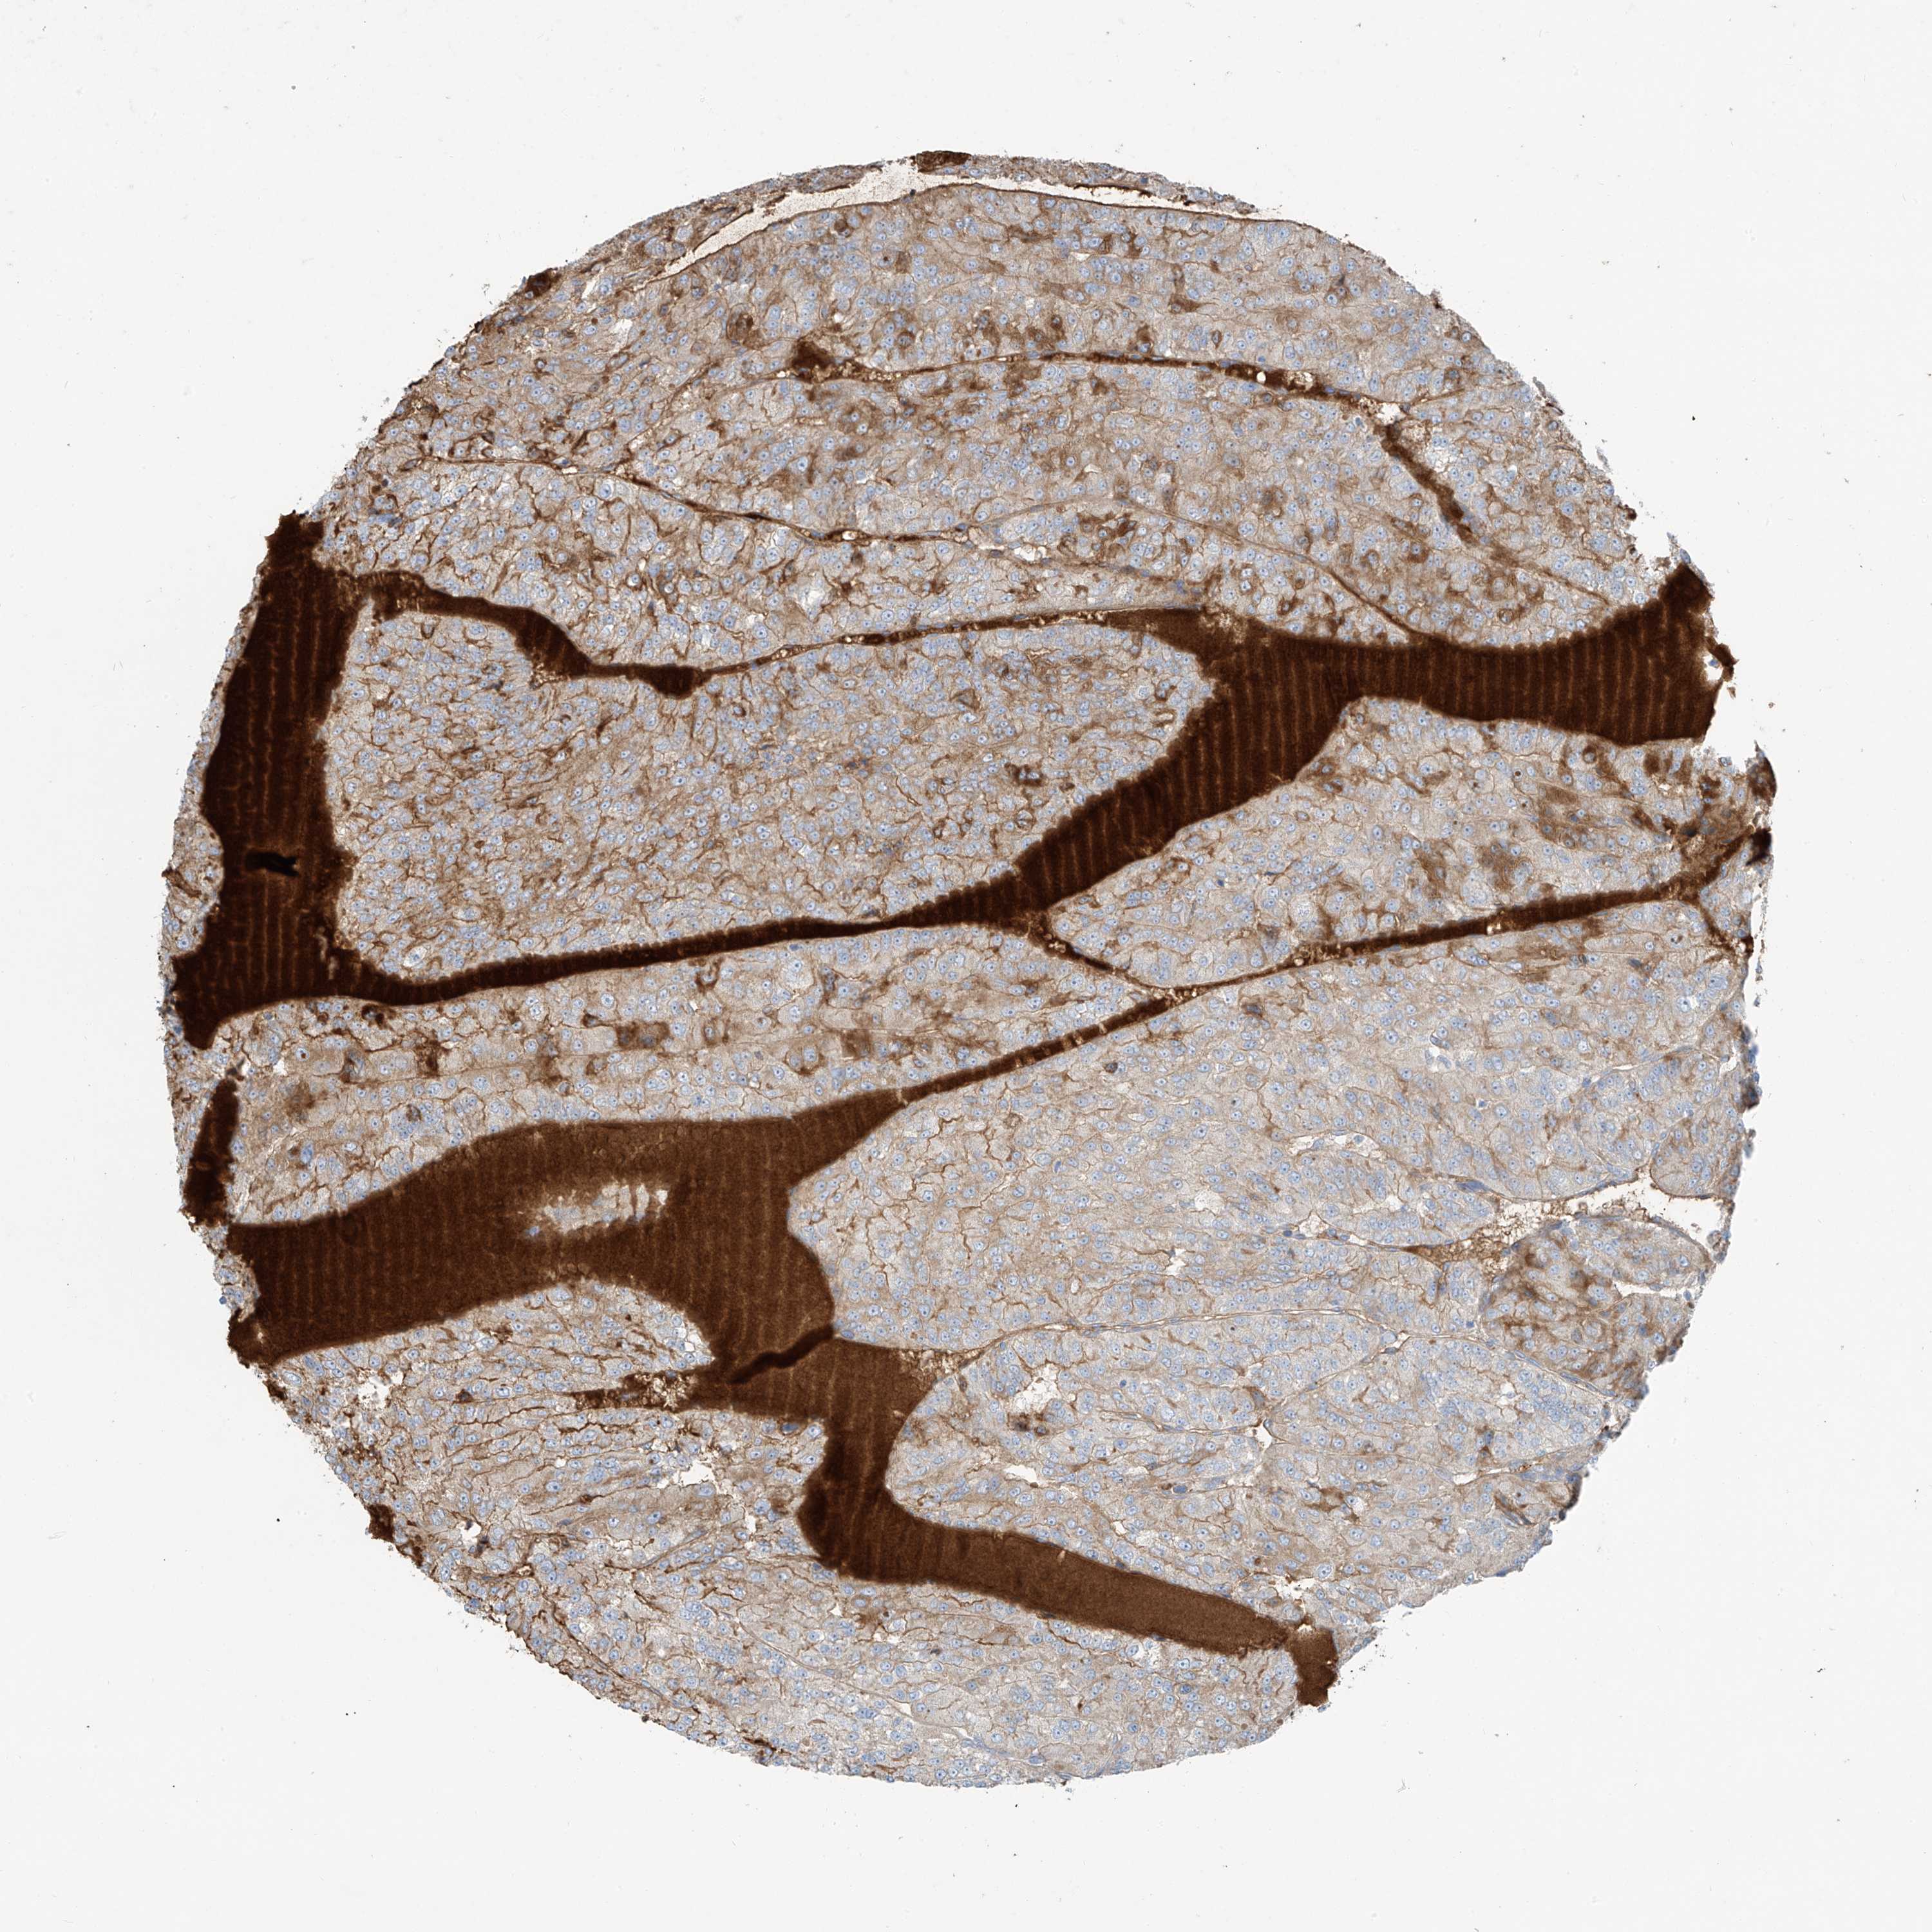

KIDNEY RENAL CLEAR CELL CARCINOMA (TCGA) - Interactive survival scatter ploti

The Survival Scatter plot shows the clinical status (i.e. dead or alive) for all individuals in the patient cohort, based on the same data that underlies the corresponding Kaplan-Meier plots. Patients that are alive at last time for follow-up are shown in blue and patients who have died during the study are shown in red.

The x-axis shows the expression levels (FPKM) of the investigated gene in the tumor tissue at the time of diagnosis. The y-axis shows the follow-up time after diagnosis (years). Both axes are complimented with kernel density curves demonstrating the data density over the axes. The top density plot shows the expression levels (FPKM) distribution among dead (red) and alive patients (blue). The right density plot shows the data density of the survived years of dead patients with high and low expression levels respectively, stratified using the cutoff indicated by the vertical dashed line through the Survival Scatter plot. This cutoff is automatically defined based on the FPKM cutoff that minimizes the p-score. The cutoff can be changed by dragging the vertical line or by entering a cutoff value in the square labeled "Current cut-off".

Under the Survival Scatter plot the p-score landscape (black curve; left axis) is shown together with dead median separation (red curve; right axis). Dead median separation is the difference in median mRNA expression between patients who have died with high and low expression, respectively. It is calculated as follows: median FPKM expression of dead patients with high expression - median FPKM expression of dead patients with low expression. This is intended to aid the user in visually exploring custom cutoffs and the associated p-scores and dead median separation.

Individual patient data is displayed and can be filtered by clicking on one or more of the category buttons on the top of the page. Categories describing expression level and patient information include: high, low, alive, dead, female, male and tumor stages. The scale of the x-axis can be toggled between linear and log-scale by clicking on the "x log" button. Mouse-over function shows TCGA ID, patient information and mRNA expression (FPKM) for each patient.

& Survival analysisi

Kaplan-Meier plots summarize results from analysis of correlation between mRNA expression level and patient survival. Patients were divided based on level of expression into one of the two groups "low" (under cut off) or "high" (over cut off). X-axis shows time for survival (years) and y-axis shows the probability of survival, where 1.0 corresponds to 100 percent.

PDGFC is validated prognostic, high expression is favorable in Kidney Renal Clear Cell Carcinoma (TCGA)

: 1.44

Average pTPM 4.0

Number of samples 521